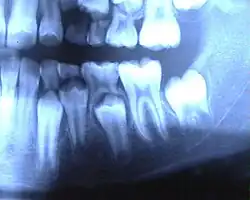

Een gebit is het samenstel van tanden en kiezen dat in de mond van een mens of de bek of muil van een dier kan worden aangetroffen.

Het gebit heeft verschillende functies. Een van de belangrijkste functies is het (voor)verwerken van voedsel. Voor dieren is het daarnaast ook een belangrijk aanvalswapen, ze kunnen er een prooi mee bijten. Aan een gebit is te zien of een dier een carnivoor, herbivoor of omnivoor is.